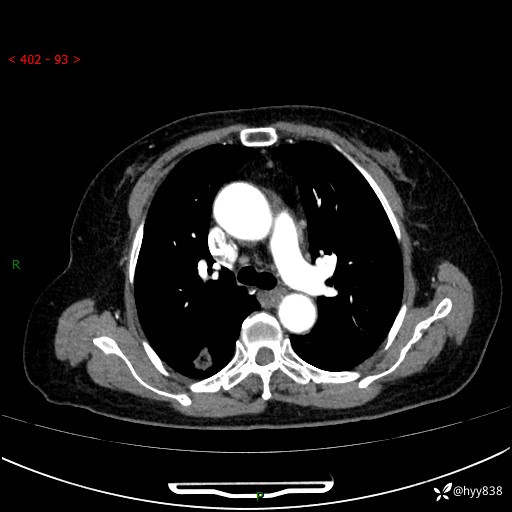

71岁/女,发现肺结节1月。偶然发现孤立肺结节,邻近叶间裂凹陷---结果公布(再回首)

【患者信息】:71岁/女

【主诉】:发现肺结节1月

【现病史及既往史】:2024年9月患者因“胆囊结石”于我院肝胆外科住院,期间完善胸部CT提示:右下肺结节灶,高危结节?感染?,病程中无畏寒发热,无咳嗽、咳痰,无活动后气短,无心慌胸闷,无胸痛、咯血,无头晕头痛,无腹痛腹泻,无四肢肌肉酸痛等不适,当时建议其择期复查。今日患者为求进一步复查就诊于我院,完善胸部CT提示:右肺结节,较前一致,遂门诊“肺部结节”收入我科。 自本次起病以来,患者精神、饮食、睡眠可,大小便正常,体力、体重未见明显异常。

【检查】:胸部CT平扫+增强